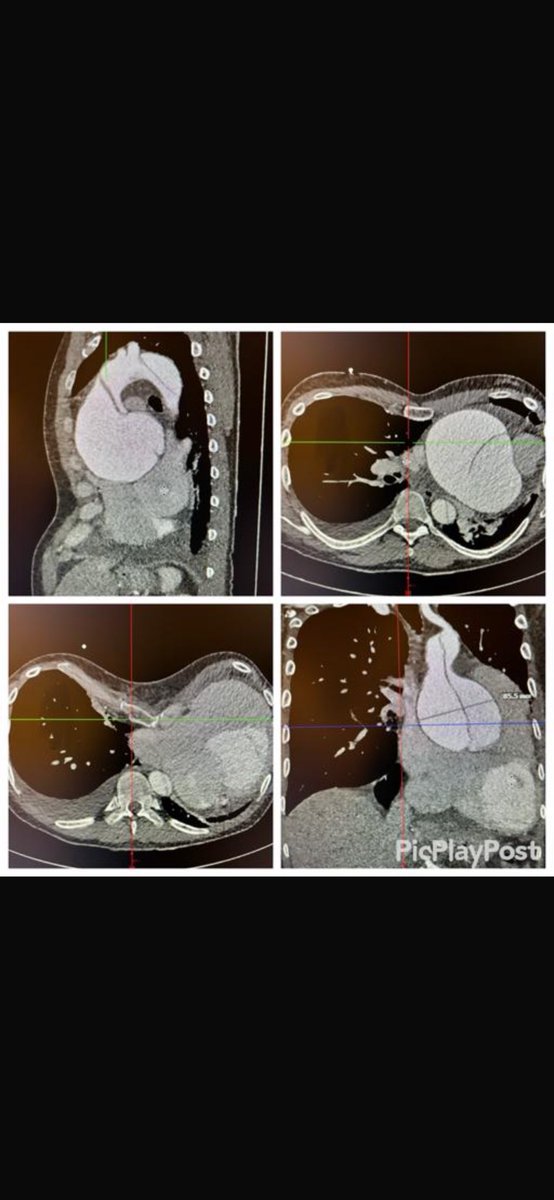

Acute Aortic Syndrome with 9cm descending aorta without landing zone for TEVAR. We offered FET+TEVAR in one session. Unilateral brain perfusion, 28 degrees, Ascending replacement, FET, reimplantion of truncus and carotis artery, debranching LSA and extranatomical bypass and TEVAR